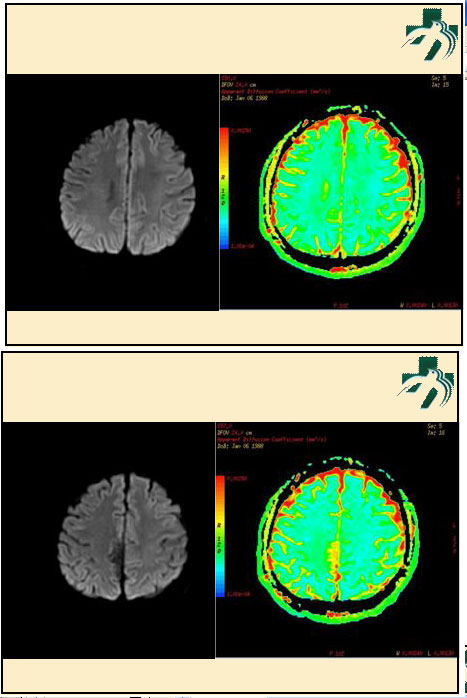

奴卡氏菌感染

第九期三博

读片会

病例之四

北京协和医院 提供

男性,22岁。自觉虫咬后皮疹、肢体麻木4月